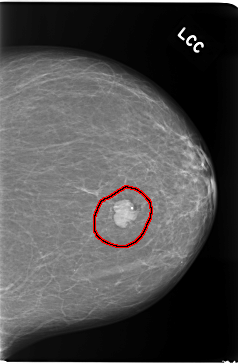

C_0082_1.LEFT_CC

LEFT_CC LINES 5824 PIXELS_PER_LINE 3808 BITS_PER_PIXEL 12 RESOLUTION 50 OVERLAY

FILE: C_0082_1.LEFT_CC.OVERLAY

TOTAL_ABNORMALITIES 1

ABNORMALITY 1

LESION_TYPE MASS SHAPE LOBULATED MARGINS CIRCUMSCRIBED

ASSESSMENT 5

SUBTLETY 5

PATHOLOGY MALIGNANT

TOTAL_OUTLINES 1

BOUNDARY